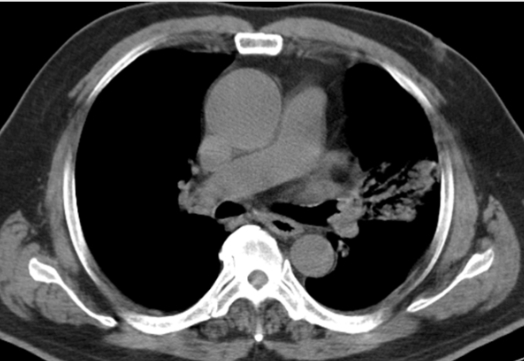

20¼¼³²ÀÚ

³»¿ø 1°³¿ù ÀüºÎÅÍ´Â ÀæÀº ±âħ°ú ÇÔ²² °¡½¿ ´ä´ä°¨, ¾ÈÁ¤

½Ã È£Èí°ï¶õÀÌ µ¿¹Ý,³»¿ø 15ÀÏ Àü, Ÿº´¿ø¿¡¼­ ±â°üÁö¿°, õ½Ä Áø´Ü.

³»¿ø 1³â 6°³¿ù ÀüºÎÅÍ ÇÏ·ç 1°©¾¿ Èí¿¬·Â

¹éÇ÷±¸ 7,330/¥ìL, Ç÷»ö¼Ò 15.4 g/dL